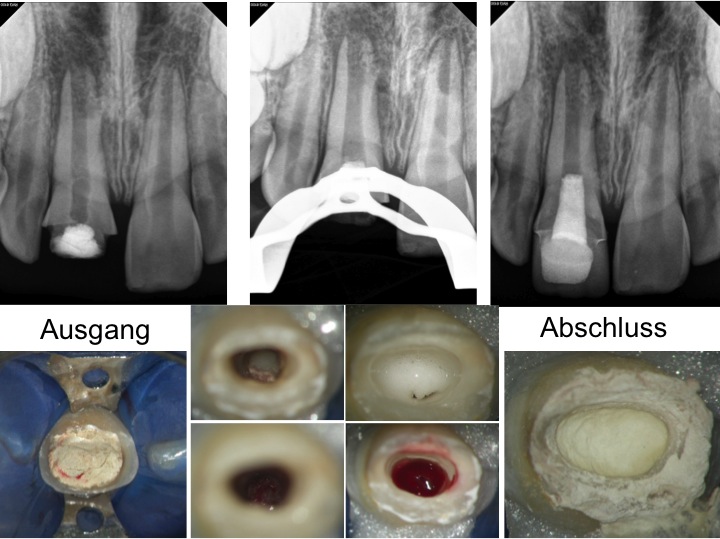

Revital1